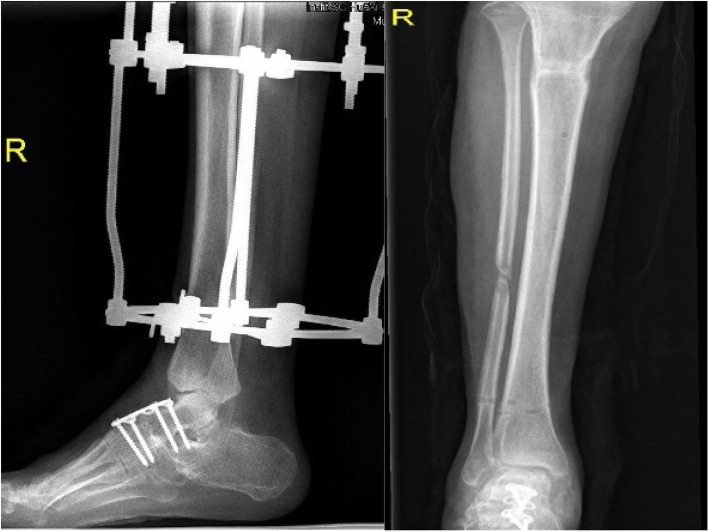

Correction began after a latency period of 7 to 10 days [22, 24]. Distraction was initiated in a rate of 1 mm/day, divided into four or six time intervals. In the period of distraction, the tension over the soft tissues, the neurovascular status, the pin site situation, and presence of pain were monitored regularly. Patients were encouraged to weight-bearing with the help of a walker or crutches to stimulate osteogenesis. Radiographs were taken every 2 weeks to observe how the distraction was progressing. The distraction speed and plan were adjusted based on the radiographic results. The heel construct and the forefoot construct were removed after 2 months. After full correction of the lower limb was achieved, the tibial frame remained stable for 6 weeks (Fig. 4). During this period of distraction, patients were encouraged to full weight-bearing and improvement of the gait by walking exercise.

Fig. 4.

The heel construct and the forefoot construct were removed after 2 months. The tibial base frame was removed when the lower limb deformity was corrected

After deformity correction, the Ilizarov external fixation was removed (Fig. 5). To maintain the correction and avoid early recurrence, an ankle–foot orthosis was routinely used in all patients for the following 6 months to 1 year [25, 26]. The foot component was removed 4 weeks after the surgery. Before removal, the hinge was unlocked in the daytime for range of motion exercise. At night, the hinge was locked with the ankle placed at 5–10° dorsiflexion.

Fig. 5.

Postoperative standing appearance of the patient